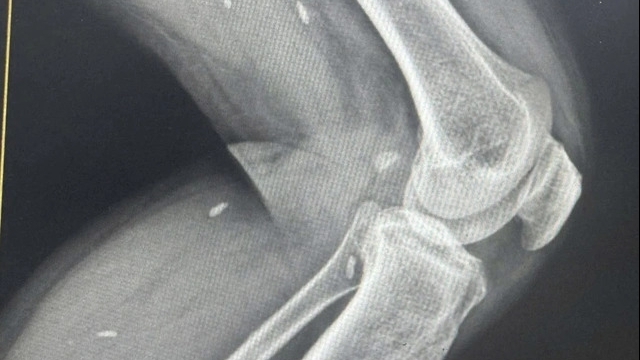

Chị được gia đình đưa đi cấp cứu tại BV Việt Đức Hà Nội. Tại đây, các bác sĩ đã phải phẫu thuật cấp cứu ngay lập tức. Khi mở ra, trong khoang ngực đã có khoảng 500 g máu cục và 500 ml nước máu đỏ tươi.

| Máu cục và máu tụ được bác sĩ lấy ra khỏi ngực bệnh nhân |

Một mạch máu đường kính 1,5 mm đang tuôn trào theo nhịp đập của tim. Các bác sĩ đã phải dùng đến dao hàn mạch chuyên dụng để cầm máu cho bệnh nhân. Sau hơn 10 ngày nằm viện, bệnh nhân đã được ra viện.